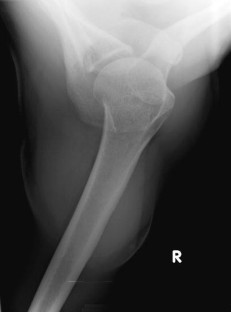

Abb. 3